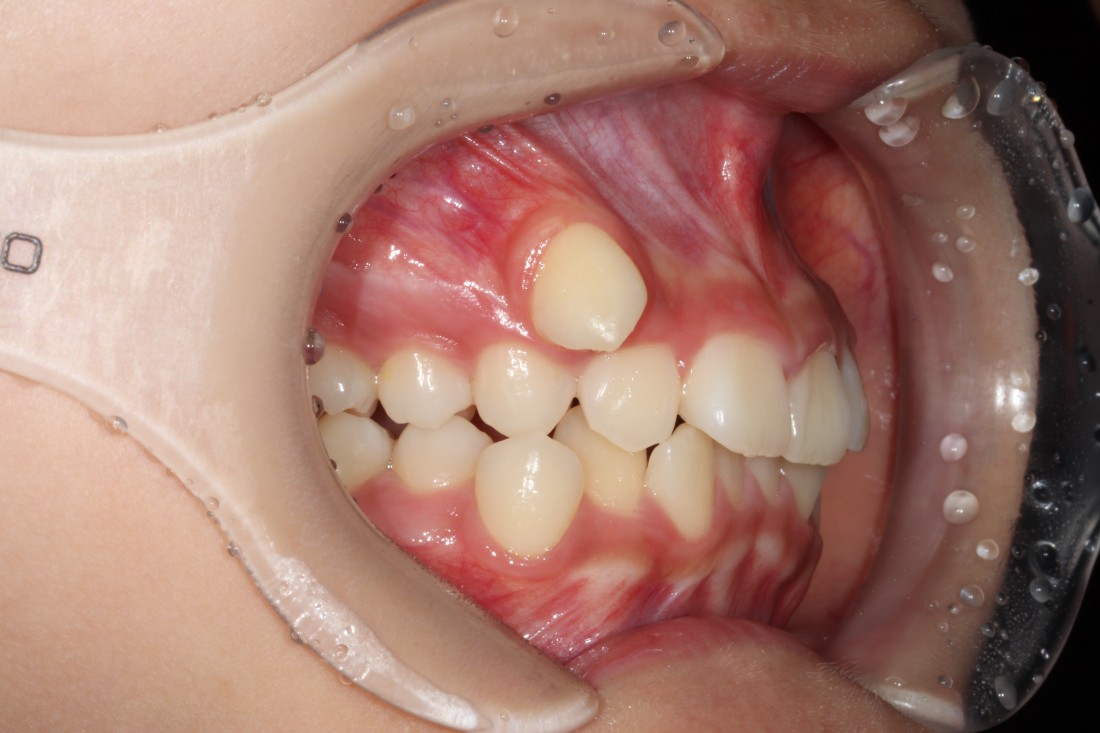

발치교정은 환자의 얼굴 균형을

맞추는 것이 핵심입니다.

잇몸이나 턱뼈 문제로

치아발치가 필요한 경우도 있기 때문에

발치교정의 핵심은

바로 '교정전문의의 실력' 이라고 할 수 있습니다.

많은 케이스를 다뤄본 의사가

가장 잘 하는 의사가 될 수 밖에 없기에

20년 넘는 교정진료 경험을 가진

광주 발치교정 치과의 교정전문의 진료로

믿을 수 있는 발치교정을 완성합니다.